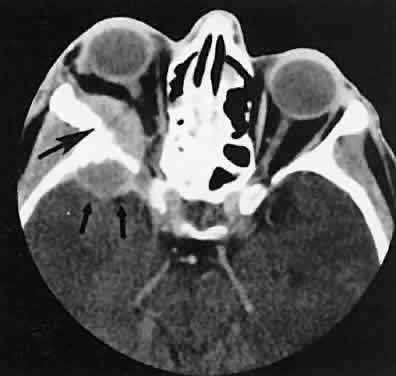

Radiographic evaluation can show either infiltrative or circumscribed masses. Some tumors display a predilection for metastasizing to certain structures, such as prostate carcinoma to bone and cutaneous melanoma to EOMs (Fig. 21). Evidence of bilateral disease at presentation ranges from 7% to 9%, with the prime example being neuroblastoma.71

Fig. 21. A. Axial view shows bilateral involvement from metastatic breast carcinoma. An amorphous infiltrative soft-tissue mass is more apparent in the right orbit, which encases the globe, producing clinical and radiographic enophthalmos. Cutaneous melanoma metastatic to the superior rectus muscle is depicted on axial (B) and coronal (C) views. A locally enhancing and asymmetric enlargement is restricted to the right superior rectus muscle. These features distinguish this lesion from Graves' orbitopathy.